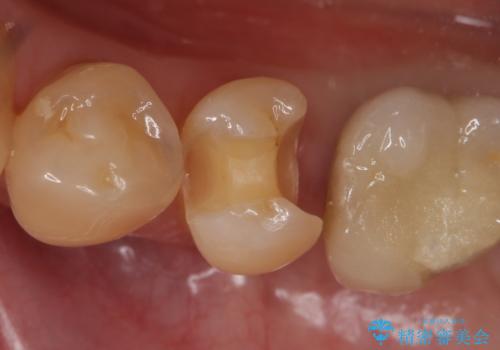

- 左下5番目の銀歯が気になるのでセラミックにしたいといらっしゃった方の症例です。

銀歯及び虫歯を除去後、セラミックインレーによる修復を行いました。